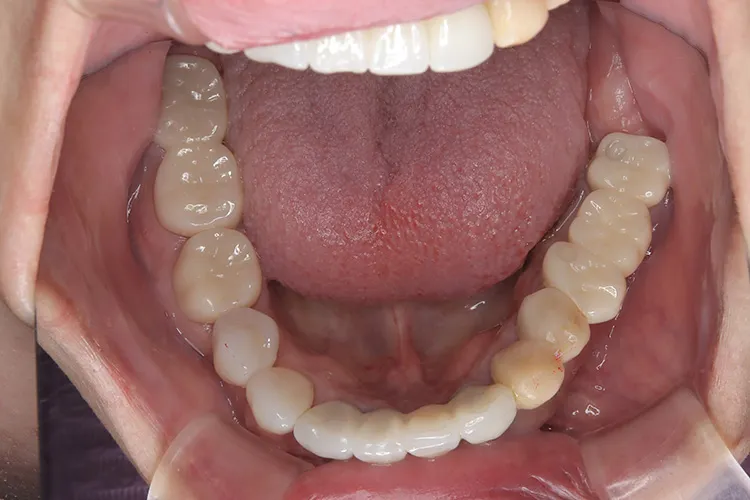

ボーンアンカードブリッジの下顎症例です。同じようにインプラント6本で上部構造を支えることができます。

左下67 欠損に対してインプラント治療を行った症例

部分床義歯を使用していたが、どうしても慣れない上にしっかり噛むことができないためインプラント治療を希望